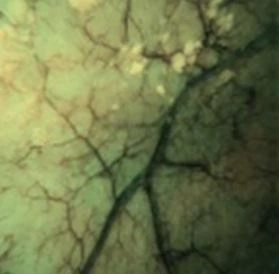

EBI / Erweiterte Bildgebung

- Verbessert den Kontrast sowie die Sichtbarkeit von Blutgefässen und Schleimhautstrukturen

- Ermöglicht eine deutlich präzisere Darstellung von Läsionsgrenzen und Oberflächenmustern

- Unterstützt den Operateur bei der Inspektion des Harnleiters auf Polypen oder Tumoren nach Abschluss der Lithotripsie